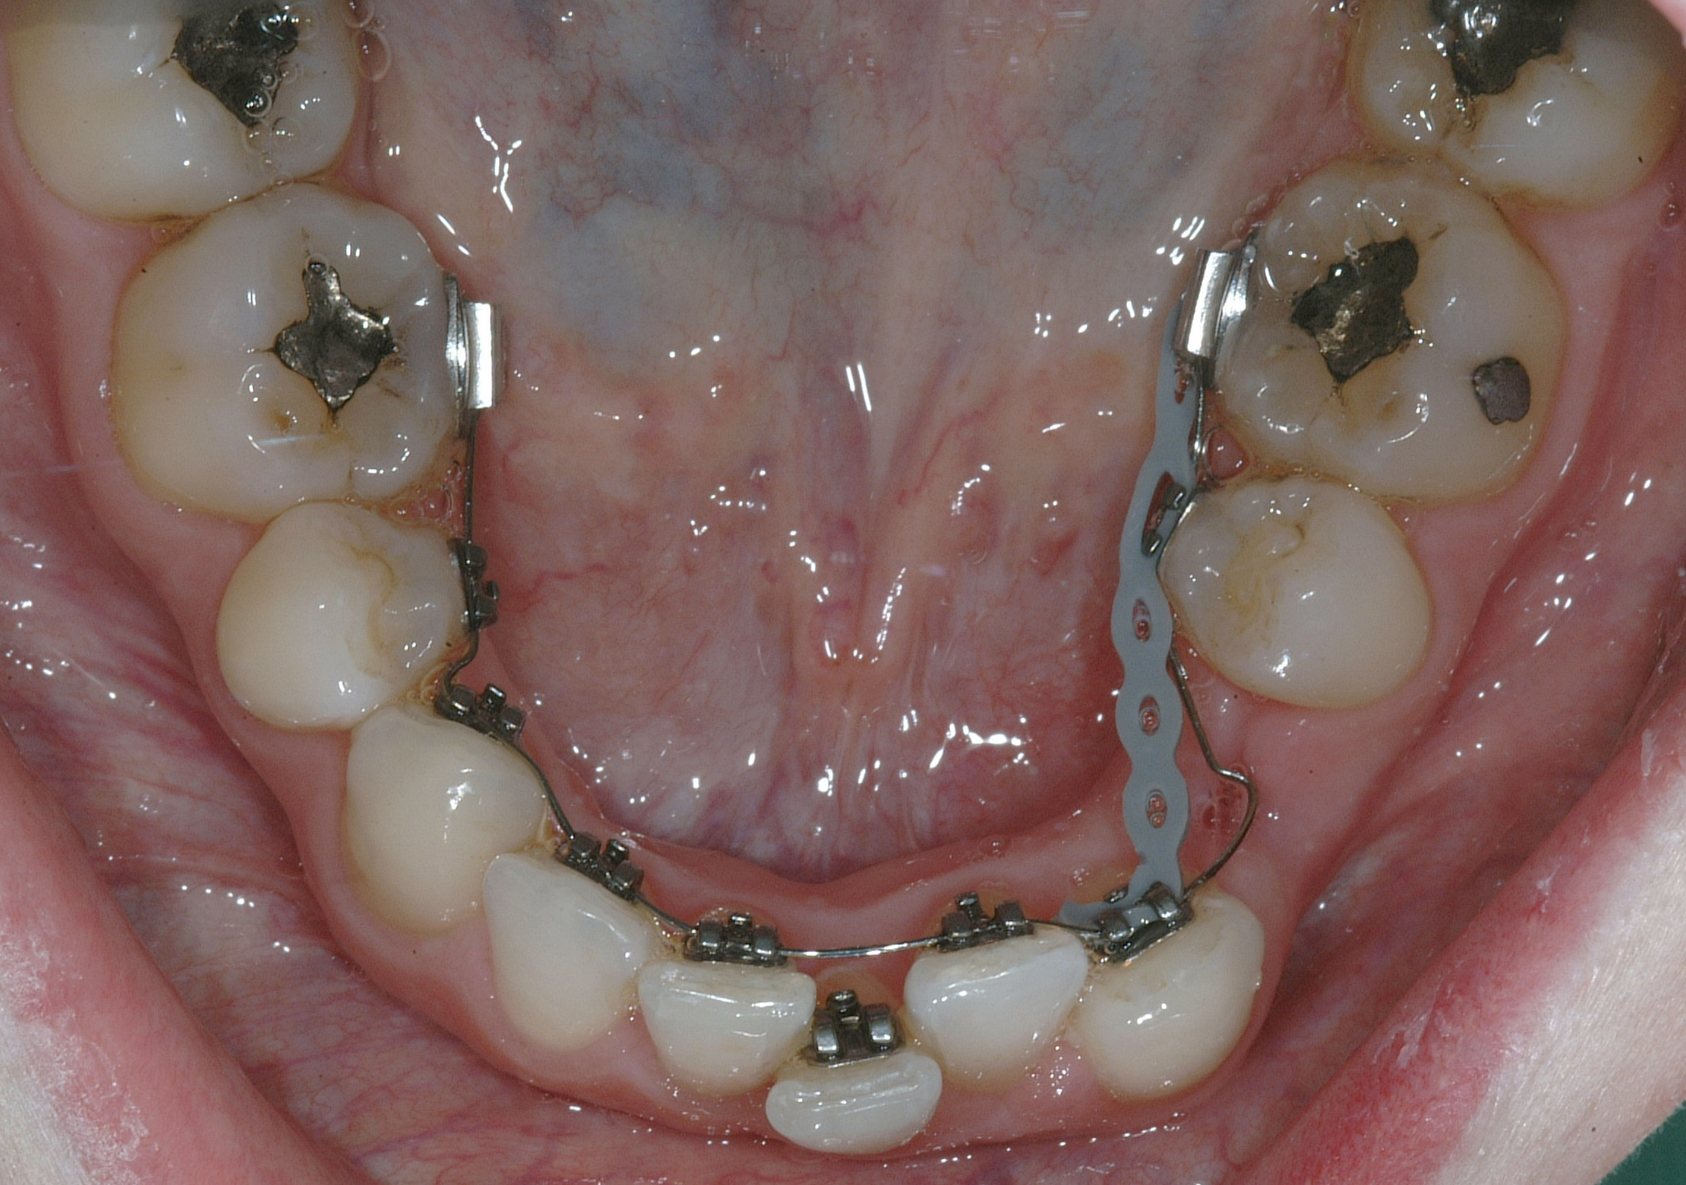

Per la chiusura dello spazio all’arcata inferiore, dopo la preliminare fase di allineamento e livellamento2, con la stessa sequenza iniziale di archi (.014” e poi .016” Nichel-Titanio), è stato temporaneamente applicato un sistema di ancoraggio ausiliario vestibolare, mediante fibre rinforzate, bondate sulla superficie vestibolare di 3.5, 3.6, 3.7 (Figura 4).

Successivamente, per controllare il movimento radicolare distale del canino inferiore sinistro (3.3), è stato applicato un sistema di forze che ha sfruttato: la forza singola distalizzante e di chiusura spazi data dalla catenella elastica con ruolo stabilizzante anche verticale su 3.3, inserita e agganciata in due segmenti, uno mesiale e uno distale, nelle rispettive alette dello slot occlusale del 3.3, e una coppia di forze di uprighting data dall’arco ortodontico .016” Nichel Titanio; quest’ultimo è stato inserito distalmente nello slot ausiliario dell’attacco linguale sul 3.5 ottenuto ripiegando verso occlusale la terza aletta gengivale, e poi nel tubo singolo sul 3.6, e mesialmente, da mesiale verso distale e da gengivale verso occlusale nello slot di 3.3, generando una flessione verticale di secondo ordine, la cui rotazione in senso linguale veniva controllata dalla catenella elastica stessa in appoggio su di esso. Il segmento di arco distale a 3.2 è stato ripiegato in senso gengivo-vestibolare (Figura 5).

Nota tecnica: una volta ottenuto il corretto posizionamento del 3.3, al fine di simmetrizzare l’arcata inferiore e centrare le linee di simmetria, è stata applicata una molla ad anse aperte tra 4.4 e 4.3 su arco .016” in acciaio (Figura 6).